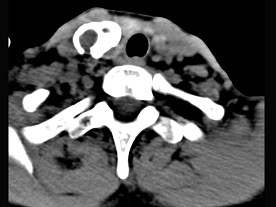

5.男性,40岁,颈部出现无痛性囊性包块2年余,CT扫描如图所示,最可能诊断为  (    )

正确答案:A